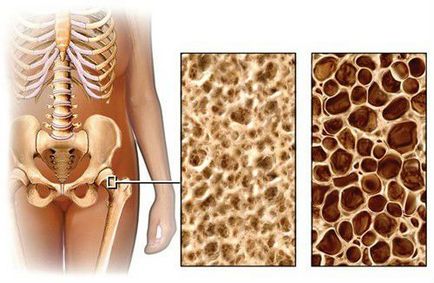

Csontritkulás - krónikus, progresszív szisztémás metabolikus csontbetegség karakter vagy külön klinikai szindróma bizonyos betegségek alapuló csökkentésére csontsűrűség és zavar normál szerkezetének. Ez ahhoz vezet, hogy a csont törékenysége és jelentősen megnövekedett törési kockázat a csontritkulásban szenvedő.

Bal mutatja normál szerkezetének a csont, és a megfelelő - a szerkezetét csontritkulás